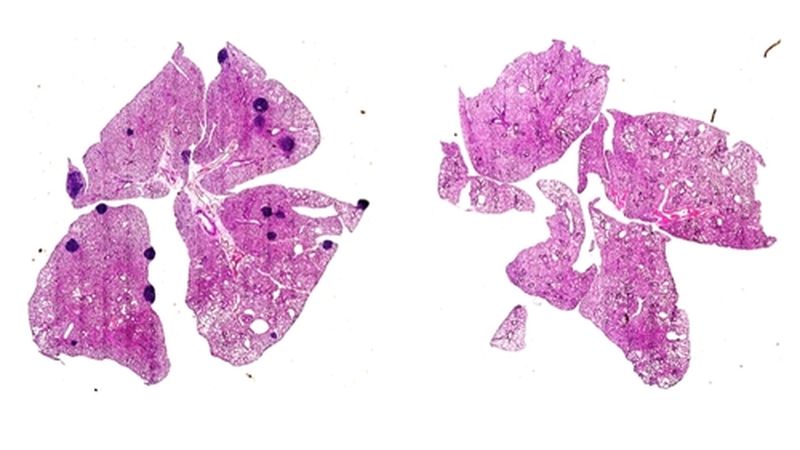

일반적인 유방암 생쥐 모델(왼쪽)의 폐에는 전이성 암(짙은 색 부분)이 발생했으나 아스피린 투여 시 억제되는 혈소판의 응고 인자인 트롬복산 A2(TXA2)에 의한 T세포 면역 억제에 관여하는 단백질(ARHGEF1)이 결핍된 생쥐에서는 전이가 일어나지 않았다. [Jie Yang 제공. 재판매 및 Db 금지]

연구팀은 먼저 생쥐의 유전자 810개를 검사해 암 전이에 영향을 미치는 유전자 15개를 발견했다. 특히 특정 단백질(ARHGEF1)을 만드는 유전자가 결핍된 생쥐는 다양한 원발성 암이 폐와 간으로 전이되는 비율이 낮았다.